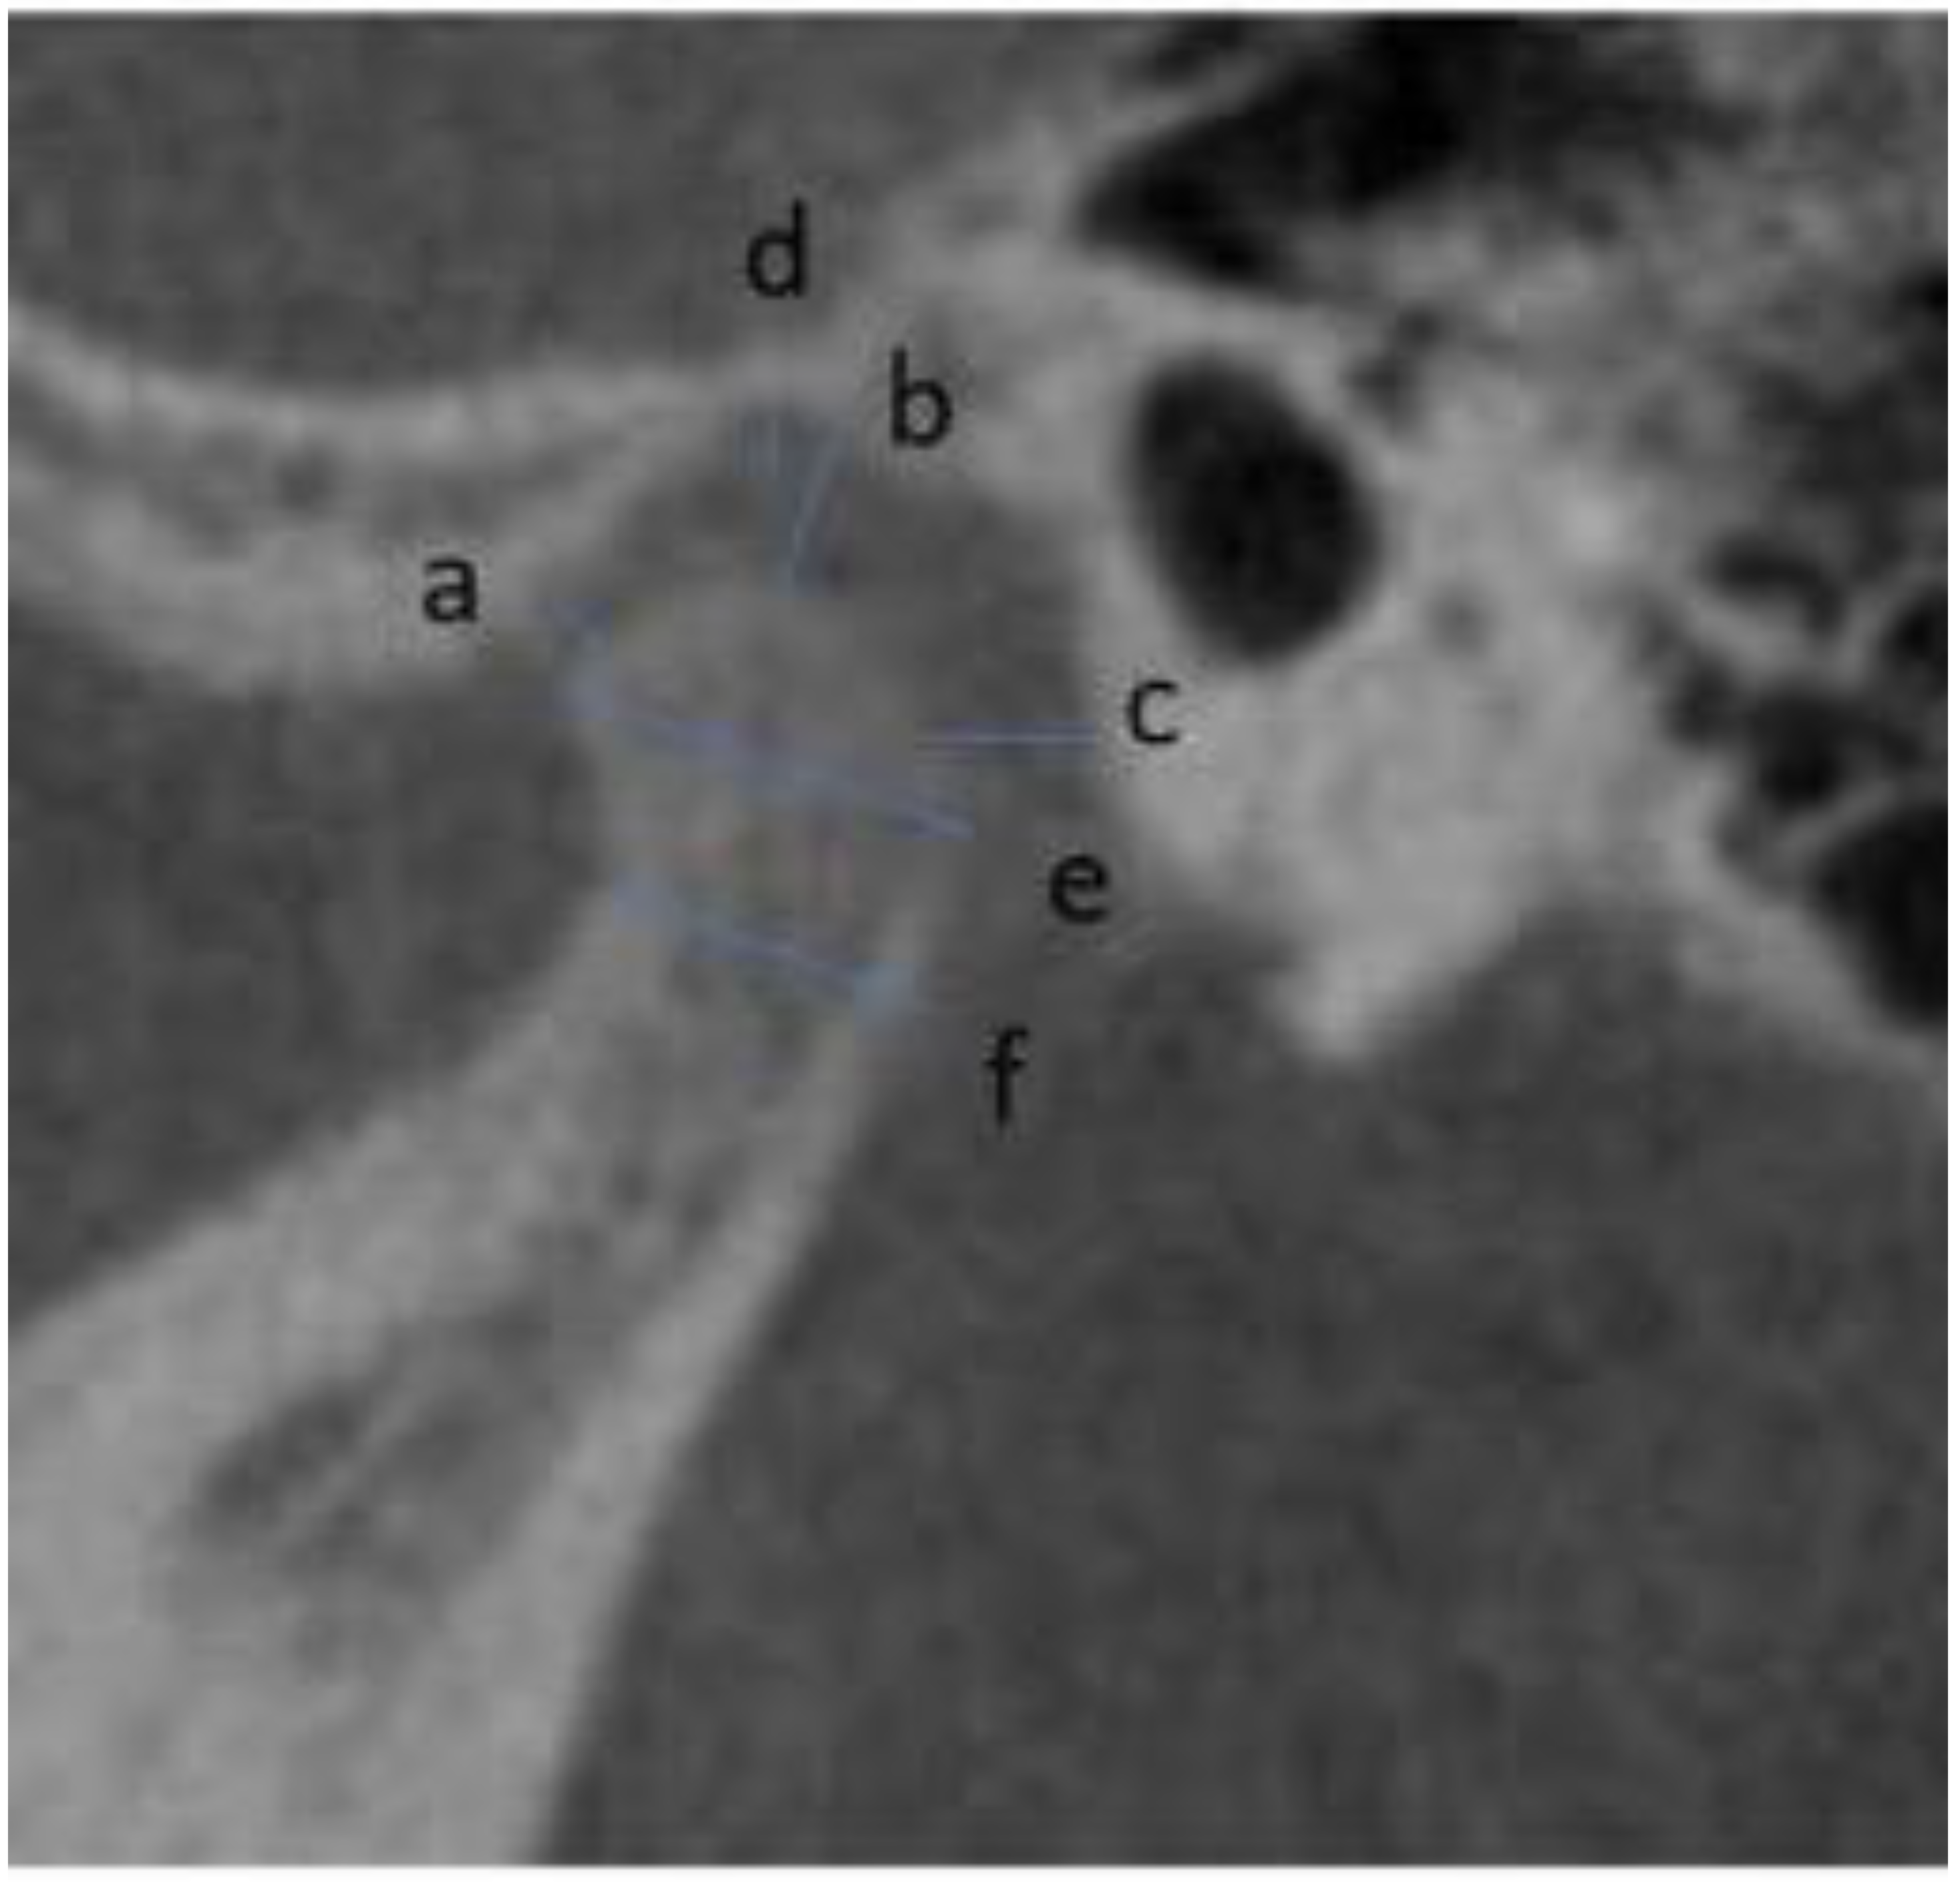

2.2. Measurements